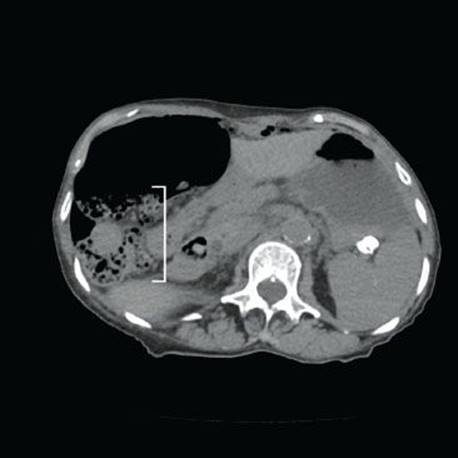

Pneumatosis cystoides intestinalis (PCI) refers to cyst-like structures impregnated with gas and lined by macrophages and foreign body giant cells. These structures are within the bowel wall and can be visualized endoscopically and radiographically (Figs. 4.256–4.262). Up to 85% of PCI cases are secondary to an iatrogenic procedure, mechanical, bacterial, metabolic, or pulmonary dysfunction.123 An association with collagen tissue disorders, AIDS, and glucorticoids has also been reported. While numerous theories of origin exist, the prevailing view is that increased intraluminal pressures force gas through damaged mucosa, and a subsequent tissue response manifests as a foreign body giant cell reaction. PCI can be seen anywhere along the tubular GIT, but most cases involve the bowel (colon = 78%, small bowel = 57%).123 Patients are usually asymptomatic. When pneumatosis is identified, it is important to assure that there is not other pathology in the resection that may have initiated the rather eye-catching pneumatosis&emdash;a classic example is scleroderma (which results in sclerosis of the muscularis propria and obstruction). CMV infection is also detected in some cases. Complications include obstruction, volvulus, intussception, ischemia, and perforation. Treatment is aimed at correcting the underlying disease or conservative medical therapy, where possible. See also, Pearls & Pitfalls, Granulomatous Pattern, this chapter.

Figure 4.256 Pneumatosis cystoides intestinalis (PCI). This patient had a longstanding history of chronic obstructive pulmonary disease (COPD) and presented with abdominal pain. The imaging study shows numerous air pockets within the bowel wall. The bowel wall has a spongelike or swiss-cheese-like foamy appearance on imaging (bracket). COPD causes PCI secondary to increased intraabdominal pressure, which forces gas into the bowel wall.